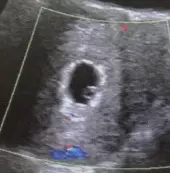

假孕囊

轮廓不规则,与孕龄不符,呈壁薄的单环状暗区;假孕囊一般位于子宫腔正中央;假孕囊随孕龄不生长或反见缩小;附件区可出现孕囊或包块;宫内刮宫刮出的组织中,未见绒毛等胚胎组织,只见蜕膜组织。